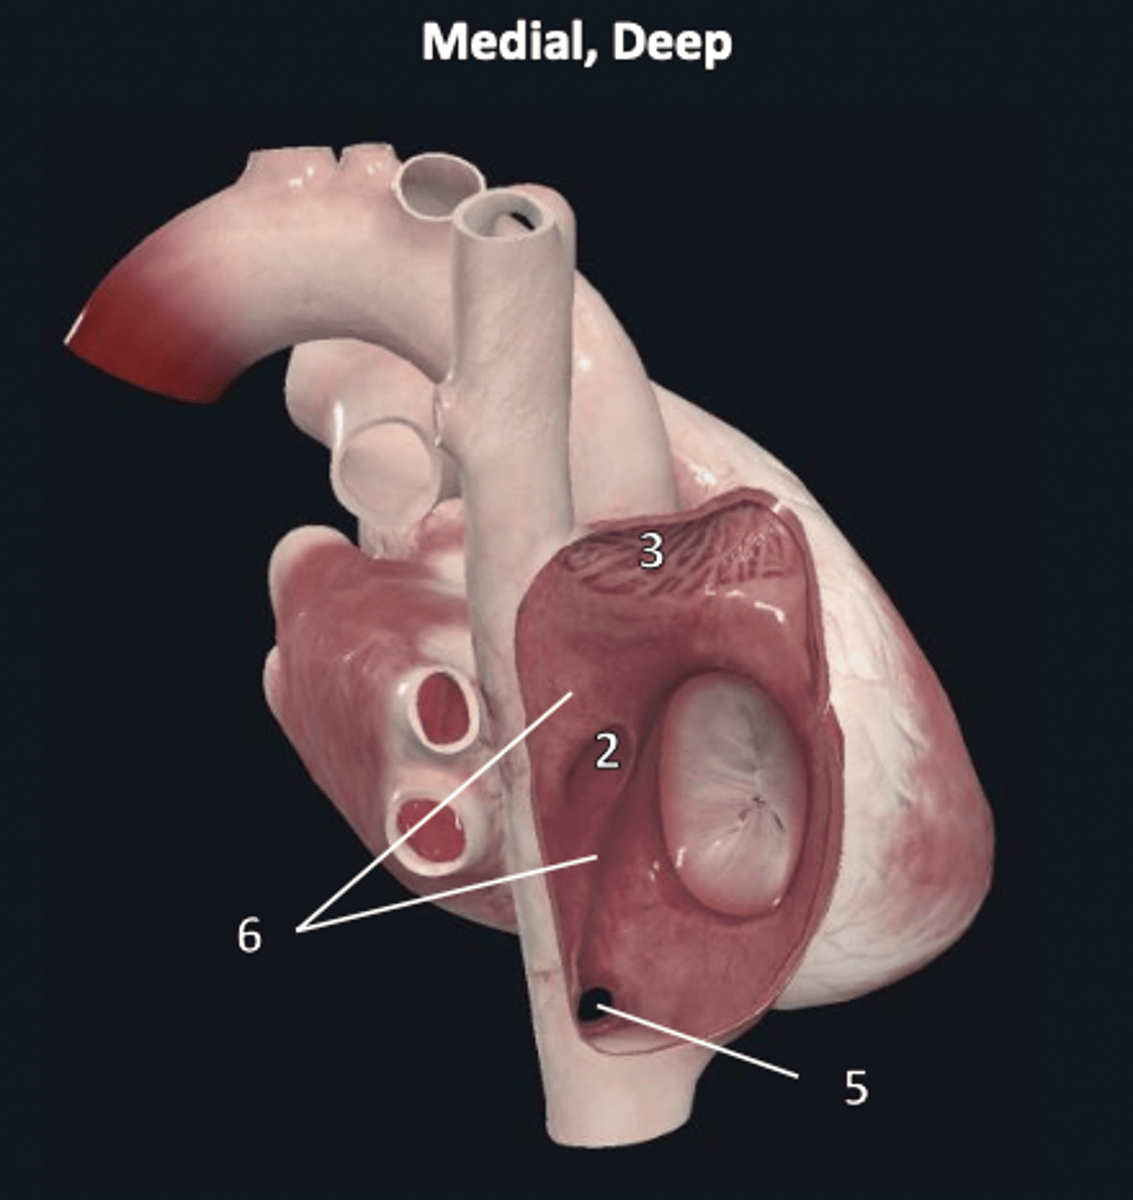

right ventricle

1

trabeculae carneae

2

septal papillary muscle

3

anterior papillary muscle

4

inferior papillary muscle

5

chordae tendineae

6

moderator band

7

tricuspid valve

8

pulmonary semilunar valve

9

interventricular septum

10